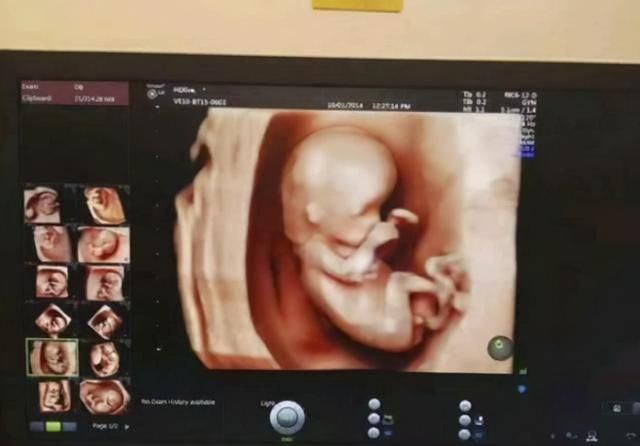

怀孕最初的几周,大家被孕吐困扰着,接着在各种产检中折腾来折腾去,部分准妈妈开始焦虑和不安。进入孕期的28周,也意味着迈过了孕期的一个分界线。

进入孕28周,准妈妈正式迎来孕晚期,肚子越来越重,需要格外注意的事情也有所变化。

理性分析汪女士婆婆说的话,28周的胎儿身体发育确实越来越成熟,包括一些畸形的检查也都通过了。